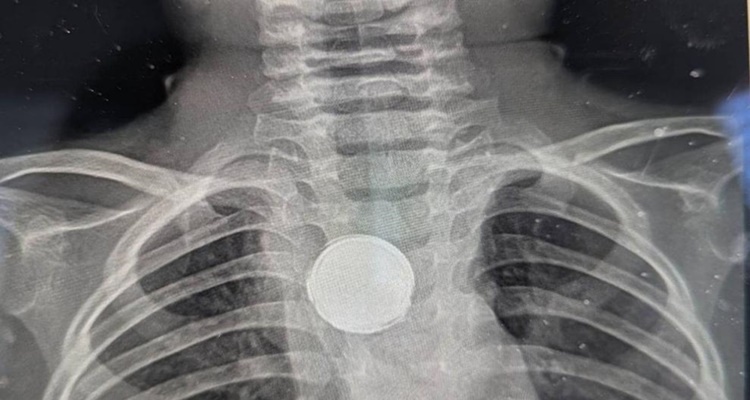

Erica lo volvió a llevar al médico, pensando que fuera un problema de reflujo. Pero la madre, sabía que pasaba algo más. Decidió llevarlo a otro pediatra que pidió una radiografía de Luke. "Les vi poner una mirada extraña", dijo Erica. Los médicos le preguntaron si su hijo había tragado una moneda o si usaba un collar con un botón, a lo que respondió que no, siendo Luke llevado a urgencias inmediatamente.

"(Los médicos) decían, 'no hay forma de que sea una pila porque comienzan a corroerse en tan solo dos horas'", prosiguió su relato Erica. Los médicos dijeron a los padres de Luke que tenía algo plateado en el pecho, pero que sería peligroso sacar ese objeto sin una cirugía completa.

Empezó la operación y una hora después, uno de los médicos salió y le dijo a Erica que habían encontrado una batería de litio pegada al interior del esófago de Luke. La pila de botón estaba envuelta en cinta aislante, y se cree que eso fue lo que le salvó la vida al niño, según los médicos.